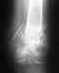

Не могу шевелить большим пальцем и у свода стопы образовались болезненные уплотнения.Прошло 3 месяца ходить не могу,наступая на ногу болят уплотнения.